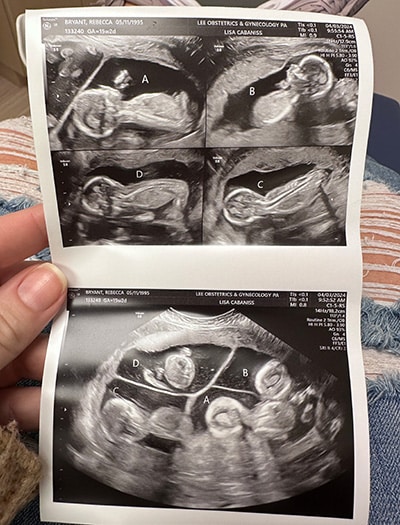

In February 2024, Becca and Lavareis Bryant attended a routine ultrasound appointment in their hometown of Auburn, Alabama. With three older children, the couple was excited to get their first glance at their fourth baby. They were also nervous as they had recently experienced a miscarriage.

“The ultrasound tech started moving the machine around, and I started to notice one big spot and two smaller ones,” Lavareis said. “The next thing I know, she’s counting — 1 … 2 … 3 … 4!”

They stared at each other in disbelief. The final baby of the family was actually four babies. Becca’s pregnancy was now considered high-risk. Her obstetrician referred her to the UAB maternal-fetal medicine team, who specializes in high-risk obstetrics and unique pregnancies.

Multiple pregnancies are rare, with twins occurring in one in 80 and quadruplets occurring in one in 700,000. Becca had a trichorionic quadra-amniotic pregnancy, meaning there were four babies and four sacs but only three placentas.

“The odds of this specific type of quads are around one in 7 million,” said Ayodeji Sanusi, M.D., Becca’s maternal-fetal medicine physician at UAB. “Three eggs were fertilized; but one split, making two of the babies identical and two fraternal. It also added on to the complex and high-risk nature of her pregnancy.”